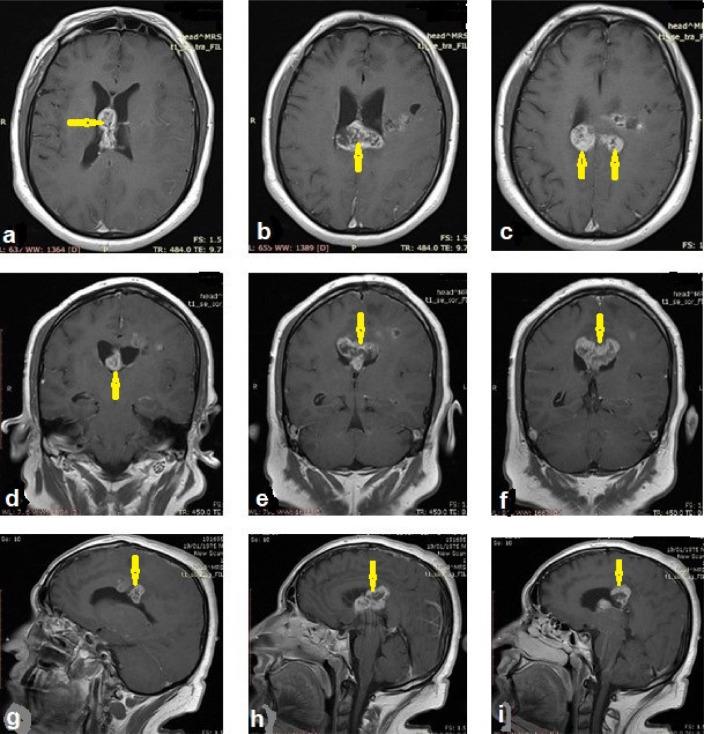

Diffuse astrocytoma is an infiltrating type of glioma (World Health Organization grade II), which even with histopathology, is difficult to diagnose. Magnetic resonance imaging (MRI) is the cornerstone for diagnoses and follow-up of brain gliomas. This report describes a case of diffuse astrocytoma in a 48-year-old man who presented with sudden right-sided weakness and repeated convulsive attacks. On brain computed tomography, the case was diagnosed and treated as an acute infarction. Ten days later, the patient returned with a total loss of consciousness. Brain MRI images revealed an irregularly outlined lesion involving the splenium of the corpus callosum that extended into the left periventricular parietal lobe of the brain with cystic foci in the septum pellucidum. Contrast-enhanced and new sequences of MRI was helpful in approach to diagnosis because of its superior tissue characterization. The histopathology results ultimately confirmed the diagnosis of diffuse astrocytoma. The patient died postoperatively.

弥漫性星形细胞瘤是一种浸润性胶质瘤(世界卫生组织二级),即使通过组织病理学检查也难以诊断。磁共振成像(MRI)是脑胶质瘤诊断和随访的基石。本报告描述了一例48岁男性弥漫性星形细胞瘤病例,该患者表现为突发右侧肢体无力和反复惊厥发作。在脑部计算机断层扫描中,该病例被诊断并当作急性梗死进行治疗。十天后,患者再次就诊时已完全失去意识。脑部MRI图像显示胼胝体压部有一个轮廓不规则的病变,延伸至左侧脑室旁顶叶,透明隔内有囊性病灶。MRI的增强扫描和新序列因其出色的组织特征有助于诊断。组织病理学结果最终确诊为弥漫性星形细胞瘤。患者术后死亡。